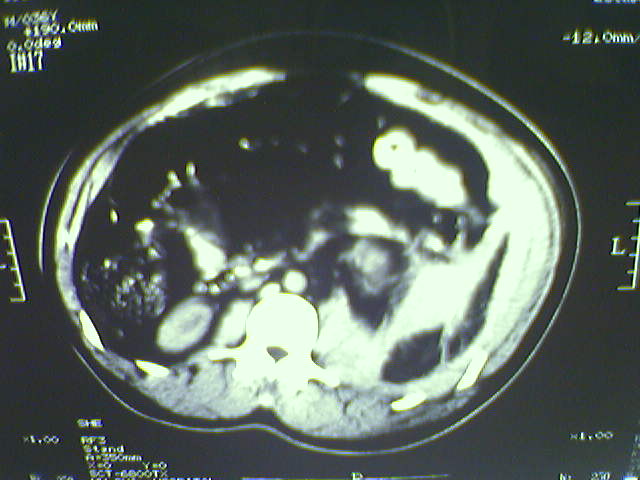

以下是引用lxq2000在2008-6-3 22:28:00的发言:[br]腹腔积液,腹壁软组织及左侧腰大肌肿胀建议mr检查。